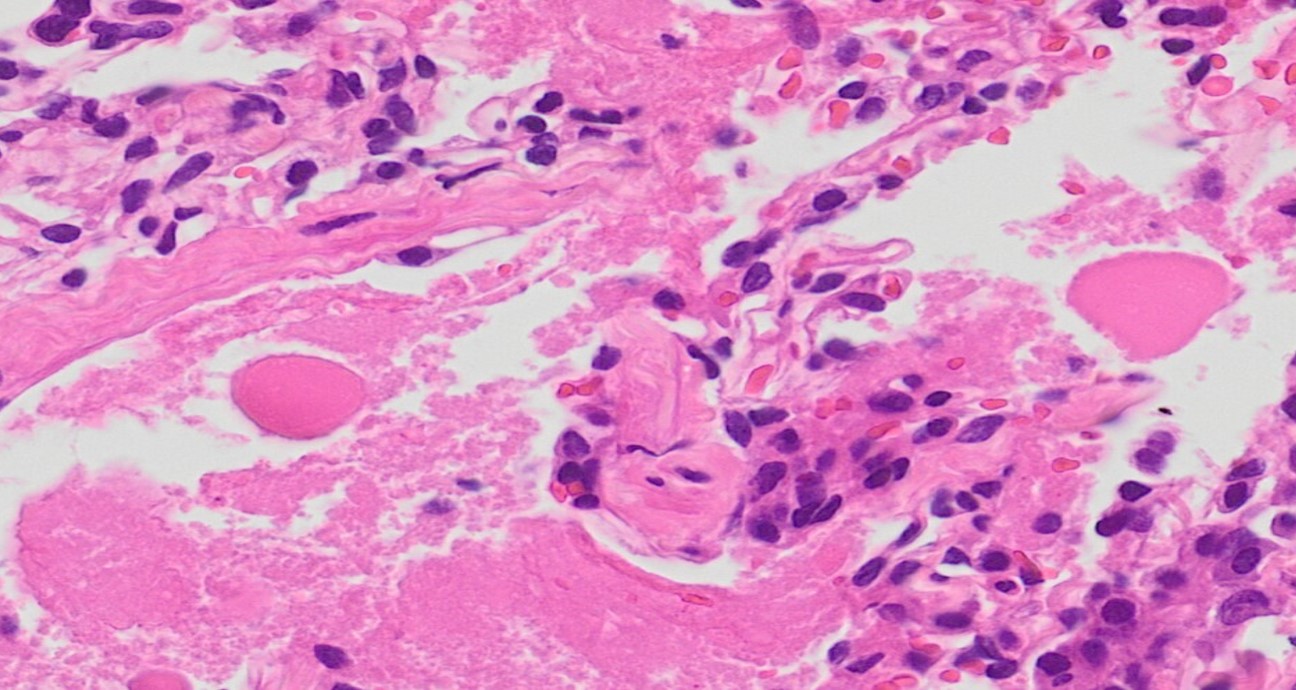

組織所見

肺胞内にエオジン好性の微細顆粒状物質が充満し、その内部には、細胞診検体で認められた類円形の無構造物質や泡沫状のマクロファージを認めた。